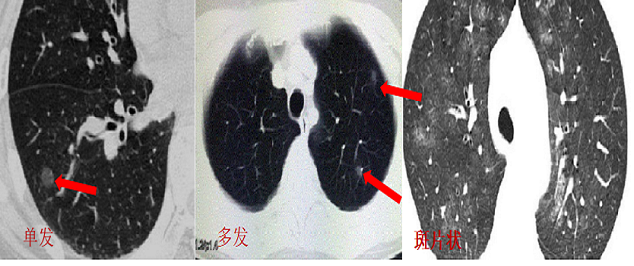

2、局限性与弥漫性GGO

局限性与弥漫性GGO是因病灶范围大小的不同而划分。局限性GGO的病灶仅表现为一个或多个结节,或大或小,其中部分大于5毫米的局限性GGO是早期肺癌的影像学表现。而弥漫性GGO表现为大片状磨玻璃影。弥漫性GGO多为良性,往往见于如下几种疾病:肺炎、肺水肿、肺出血、肺泡蛋白沉积症、肺马赛克灌注、隐球菌感染、结缔组织病、间质性肺疾病等。其GGO的影像特征有别于肺癌,往往为大片多发,弥漫,形态变化快等特点。

图三 局限性与弥漫性GGO对比